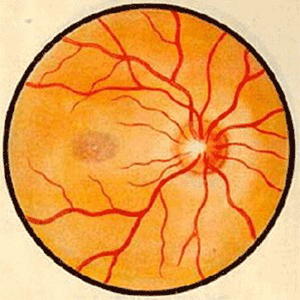

视神经病变